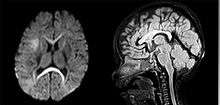

Both computed tomography angiography (CTA) and magnetic resonance angiography (MRA) have been proved to be effective in diagnosing intracranial vascular malformations after ICH.[13] So frequently, a CT angiogram will be performed in order to exclude a secondary cause of hemorrhage[14] or to detect a "spot sign".

Intraparenchymal hemorrhage can be recognized on CT scans because blood appears brighter than other tissue and is separated from the inner table of the skull by brain tissue. The tissue surrounding a bleed is often less dense than the rest of the brain because of edema, and therefore shows up darker on the CT scan.[14]